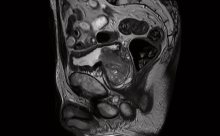

The world of medical imaging is marking a significant milestone in 2023: the 50th anniversary of magnetic resonance imaging (MRI). MRI is an efficient diagnostic procedure which uses magnetic radio waves to take internal medical images of the body, and is used to investigate and/or diagnose conditions that affect soft tissue. It assists in identifying diseases related to spine lesions, tumors, and stroke impacting the area of blood vessels and brain.